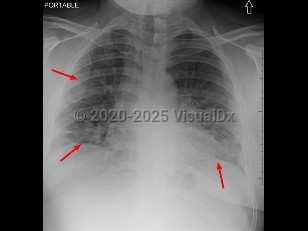

Imaging Studies image of COVID-19 - imageId=9733688. Click to open in gallery.  caption: 'Multifocal areas of airspace disease predominantly involving the lower lobes, compatible with multifocal pneumonia. SARS-CoV-2+.'

Multifocal areas of airspace disease predominantly involving the lower lobes, compatible with multifocal pneumonia. SARS-CoV-2+.